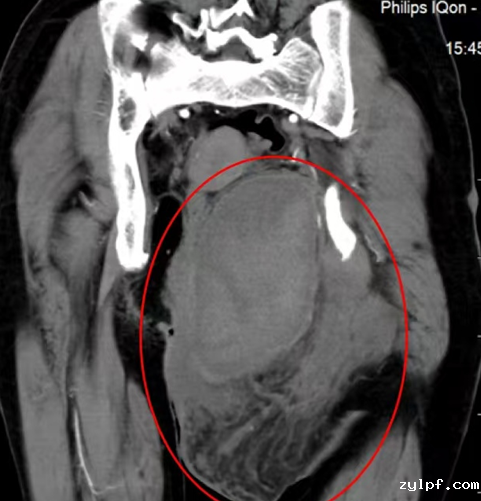

患者为54岁女性,自幼发现全身多发皮肤、皮下结节,并持续增多、变大,其中左臀部肿物尤为明显,因短时间内生长迅速、影响正常行走和排便功能来诊。患者体表可见大量散在皮肤结节、牛奶咖啡斑,MRI提示肿物信号混杂,膀胱、子宫、直肠明显受压右移,CT示该肿物跨盆腔内外,较大层面范围约13.5×8.7×13cm,密度欠均,夹杂囊变,累及左侧闭孔内肌、梨状肌、肛提肌及左侧外阴。

图片 12.png

图片 13.png图片 11.png

经过与胃肠外科、泌尿外科、妇科等多学科专家讨论,决定对该肿物进行扩大切除术。该手术难点主要在于:1.肿瘤巨大,瘤体血供丰富,且临近骶静脉丛,出血风险极高;2.肿瘤与盆腔内脏器、髂血管、坐骨神经等重要结构关系密切。因肿物与直肠下段、肛门及阴道分界不清,肛提肌受累,需切除直肠下段及肛门行永久性造瘘,首先由我院胃肠外科团队完成腹腔镜下直肠、肛门切除术+结肠造口术。经过腹腔镜探查,泌尿外科、妇科团队确认肿物未累及膀胱、子宫等其他盆腔内脏器,由骨科团队在术前3d建模辅助下完成左臀部、盆底肿物扩大切除术。

术后患者臀部外观得以修复,可正常排便、下地活动,复查CT示肿物占位效应得到明显缓解。患者及家属对手术效果表示满意,并对我院骨科团队表示感谢。